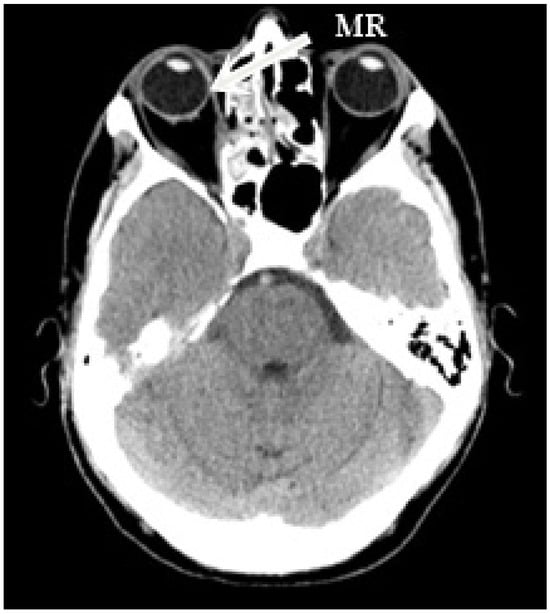

The right side was more commonly affected (five right, two left) (Figure 1). The medial orbital wall was fractured in all but one case (case 5) where the damage involved the inferior wall. Prolapse of the orbital fat and soft tissue into the field of injury were described in all patients who experienced medial wall defect. Air-filled cavities were commonly seen around the injury and the characteristic lesions for conducted endoscopic surgery were visible on all scans (Figure 2).

Figure 1. Patient 7. Axial computed tomography scan demonstrating defect in right medial orbital wall. The medial rectus was displaced medially and found adherent to the affected site, partially entrapped with defect in the lamina papyracea.